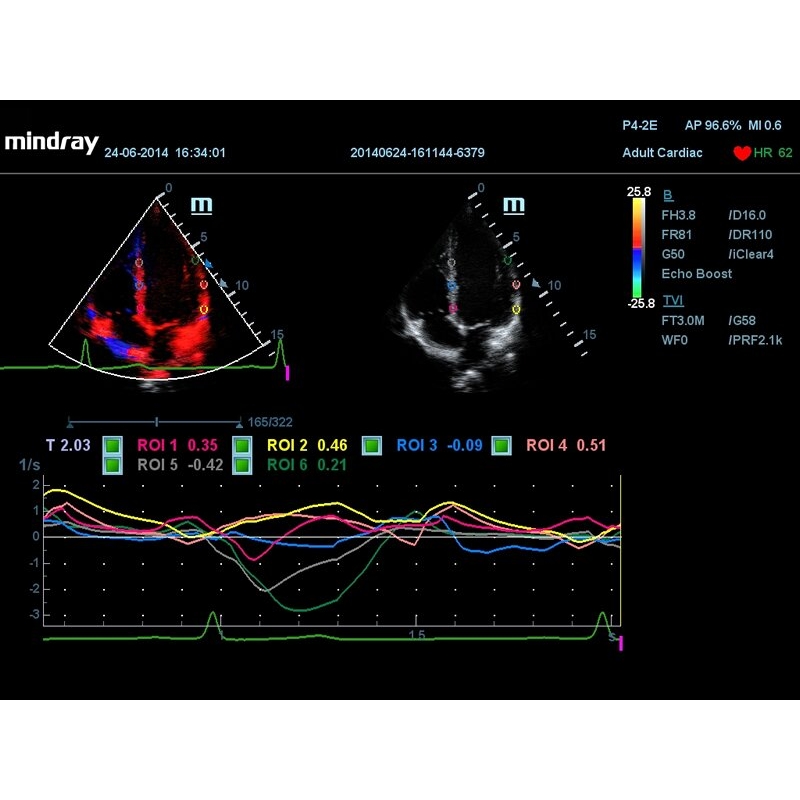

- Тканевой допплер, включая цветное картирование, импульсный тканевой допплер, энергетический тканевой допплер и тканевой М-режим;

- Программа количественного анализа в режиме тканевого допплера (необходима установленная опция TDI);

- Пакет для количественной оценки движения и деформации миокарда на основе регистрации смещения сегментов миокарда сердца (необходим модуль ввода физиологических сигналов ЭКГ/ФКГ Physio Module);